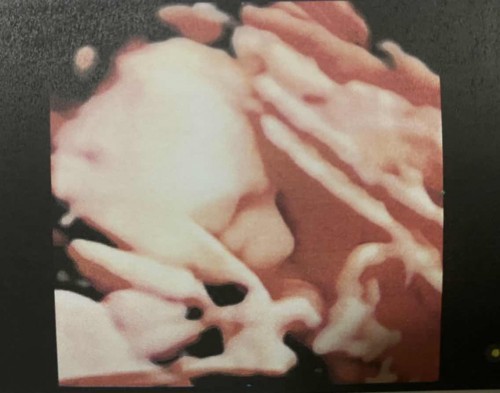

น้ำหนักลูก ในไตรมาส3

31w6D น้ำหนัก 2056ก. ช่วงสัปดาห์นี้ลูกของแม่ๆท่านอื่นน้ำหนักลูกเท่าไหร่กันบ้างคะ (เจ้าตัวแสบไม่ยอมให้เห็นหน้า >